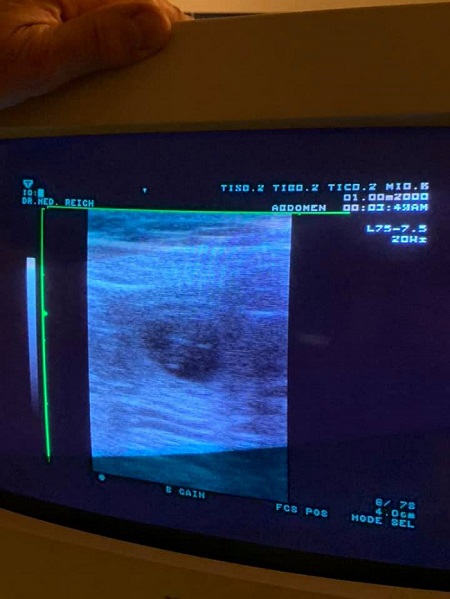

18.02.2021 Der 26. Tag der Trächtigkeit

Wir waren uns sooo sicher das unsere hübsche trächtig ist und das wurde uns jetzt auch schwarz auf weiß bestätigt!! Eigentlich war diesmal ein Ultraschall zuhause geplant, aber da das Gerät verspätet war und ich nicht mehr warten konnte, sind wir spontan zum Tierarzt. Wir freuen uns riesig über das positive Ergebnis :-)

Auch ist Melodies Gewicht trotz gleicher Fütterung um 0,9 kg gestiegen und unsere hübsche bringt getzt 27,8 kg auf die Waage und der Bauchumfang beträgt 60,5 cm.